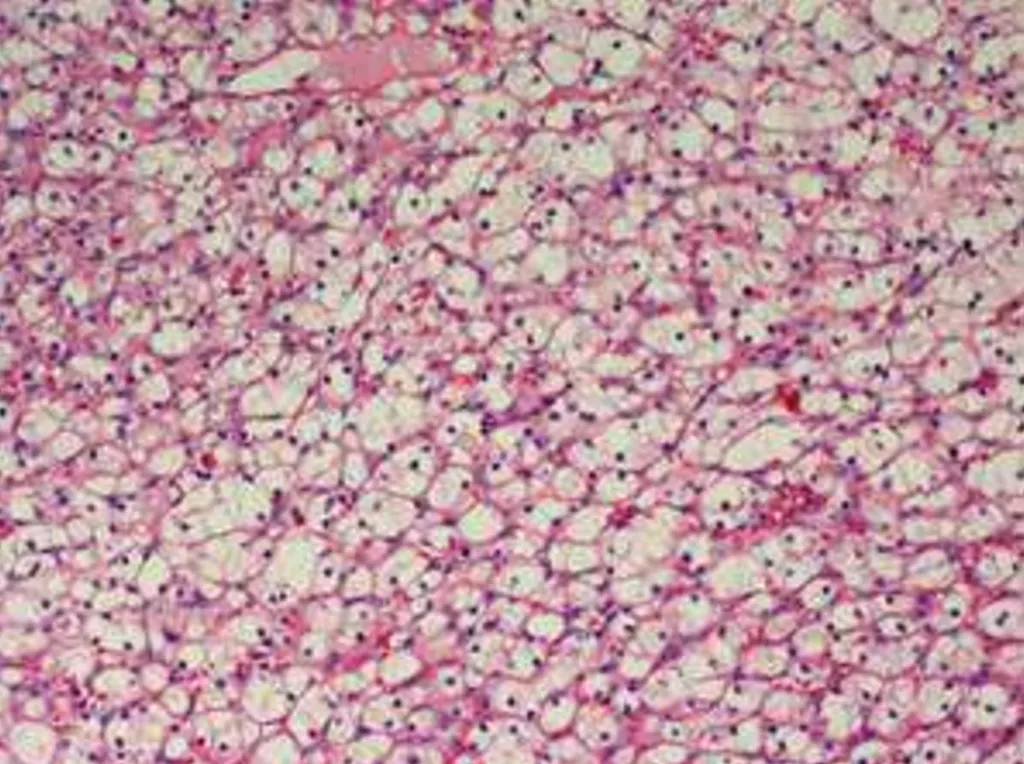

破題關鍵

這題的解題核心在於辨識圖片中的病理特徵,判斷是哪一種腎臟腫瘤,然後回想該腫瘤最常見的基因異常,並找出其中「最不可能」發生的選項。圖片中細胞呈現「透明細胞」的型態,是診斷透明細胞腎細胞癌的關鍵。